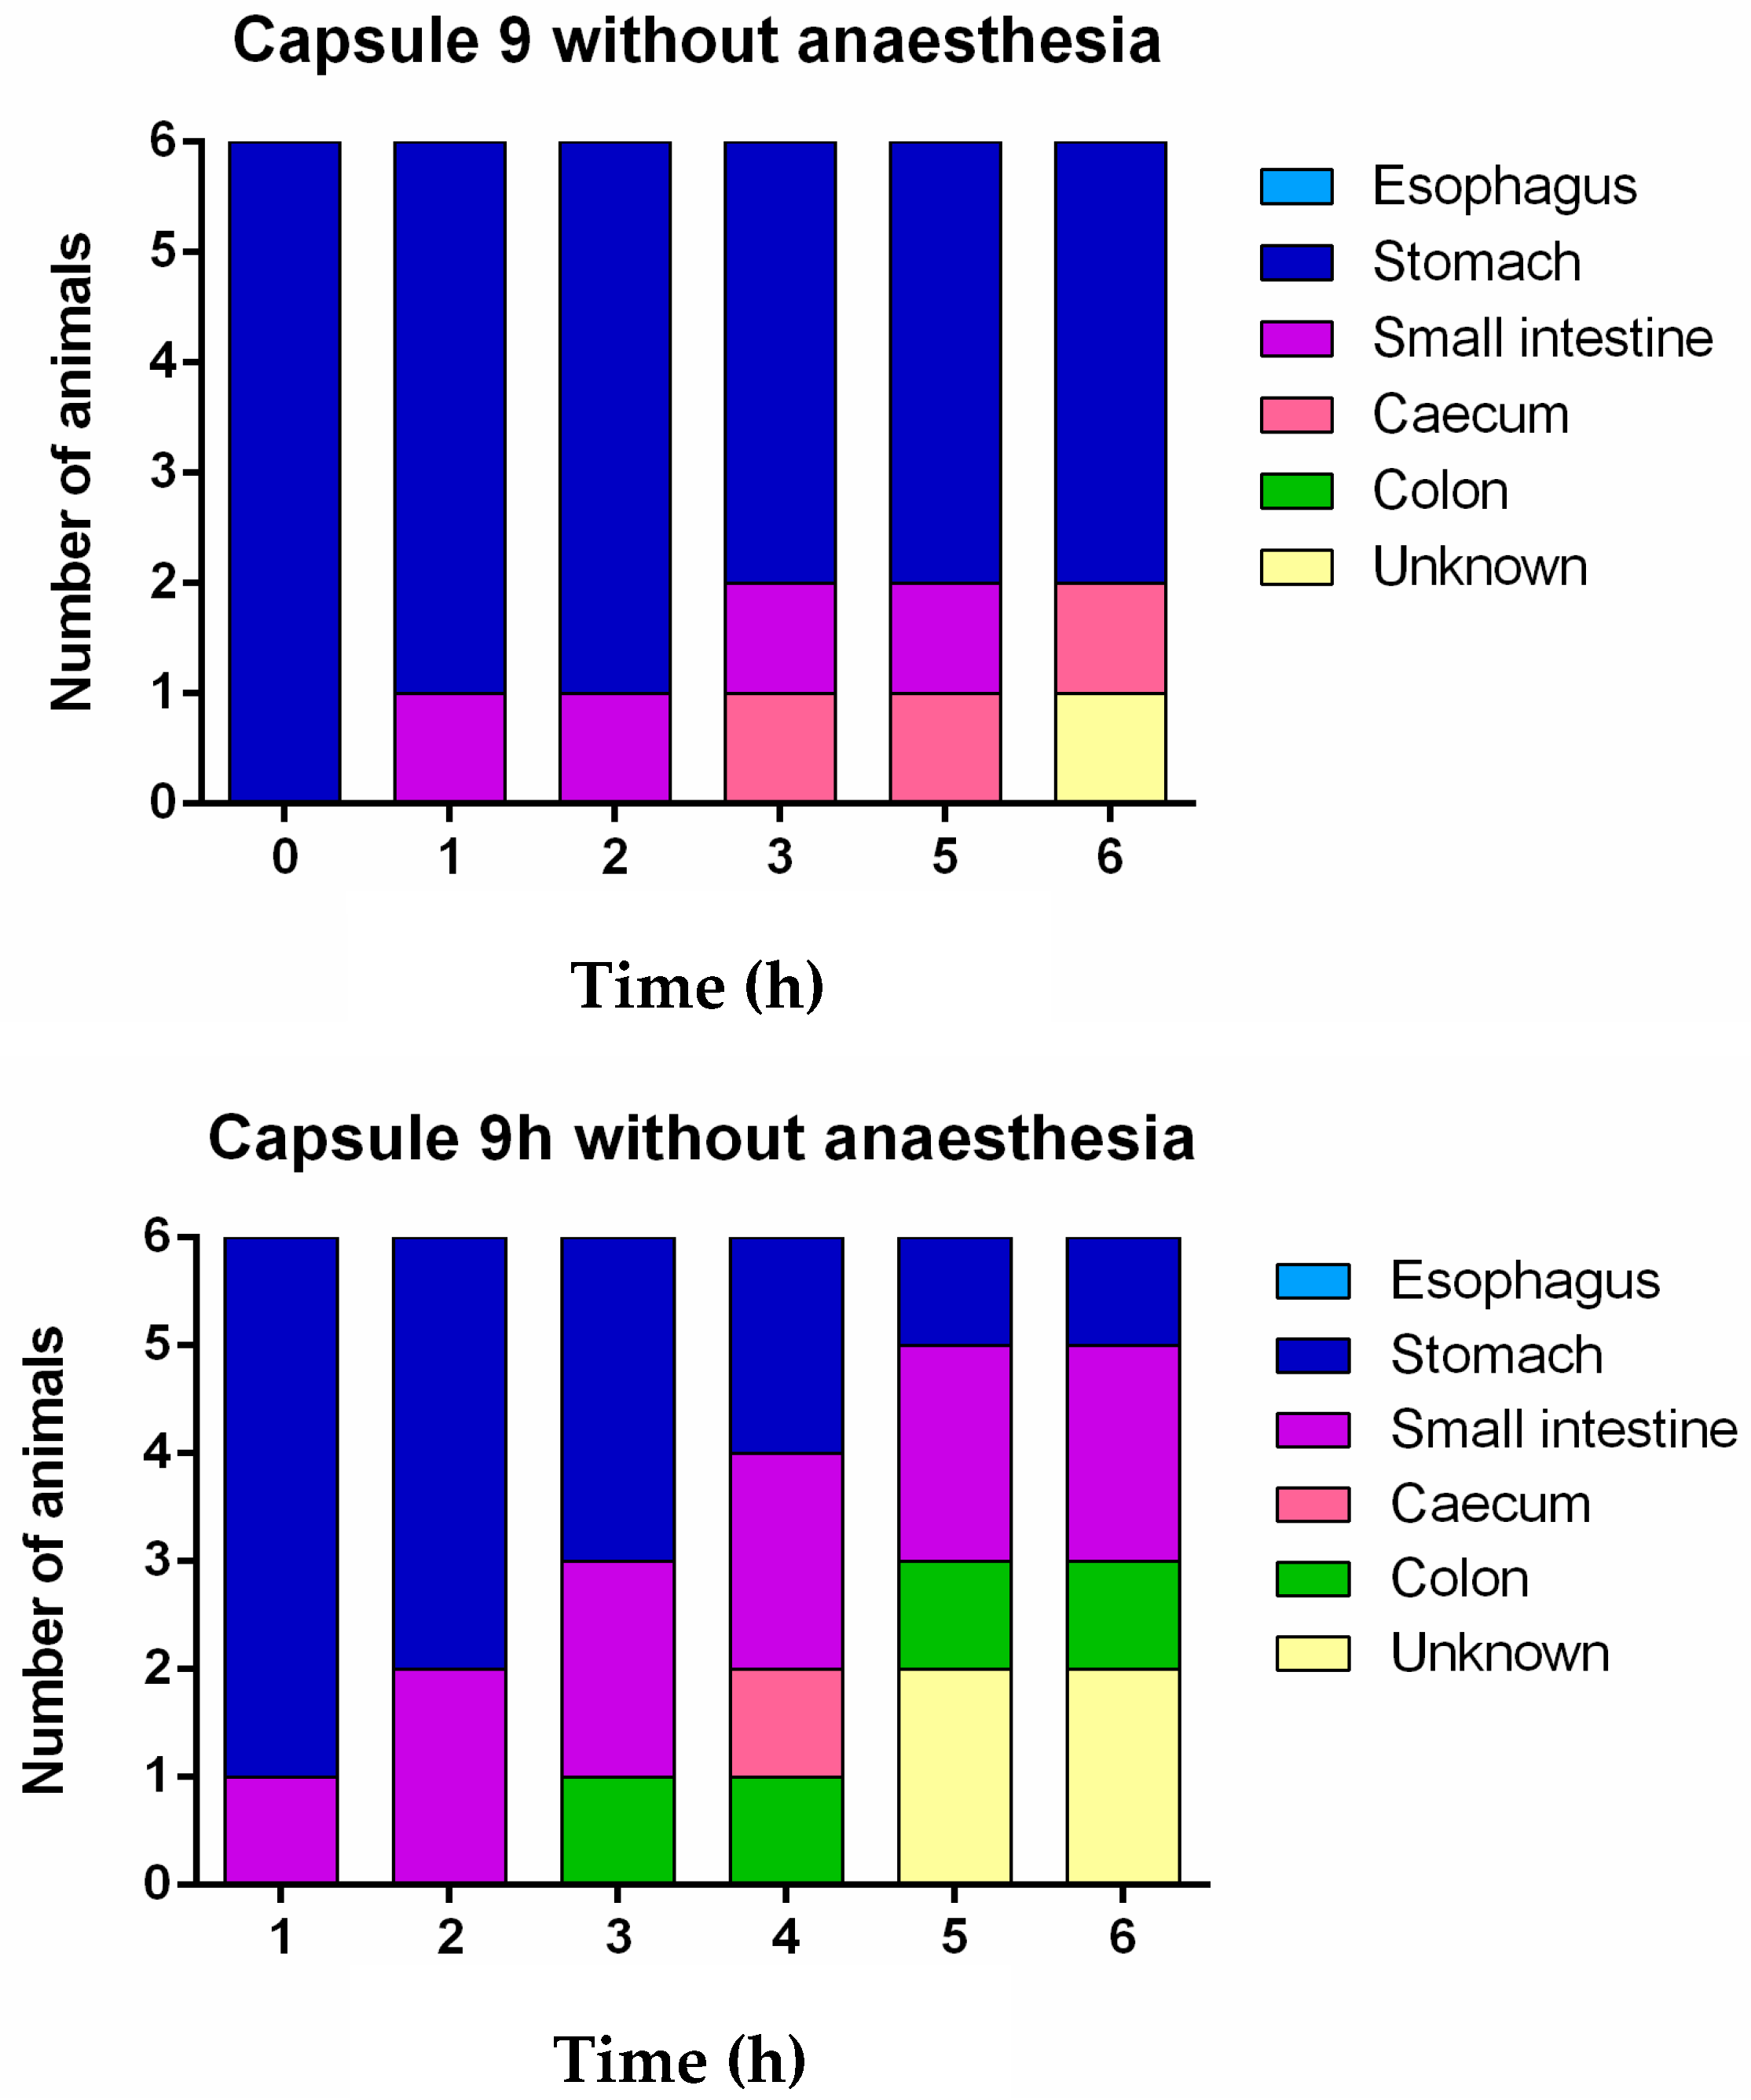

3. Results and Discussion